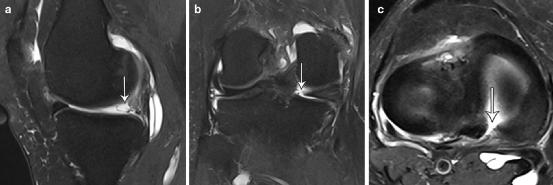

矢状T2加权脂肪抑制磁共振图像(a)显示一个拉链状损伤,在Wrisberg韧带(弯曲箭头)和外侧半月板后角之间有一个裂口。轴向T2加权脂肪抑制磁共振图像(b)显示损伤的横断面视图(箭头)

矢状面T2加权脂肪抑制磁共振图像(a)显示双三角征(细箭头),典型的半月板撕裂。轴位图像(b)显示外侧半月板后角的前脱位(细箭头)

矢状面(a)、冠状面(b)和轴面(c) T2加权脂肪抑制磁共振图像显示后内侧半月板根部附着处有“ghost sign”(细箭头)。(b)和(c)清楚地显示了后内侧半月板根部的全层撕裂